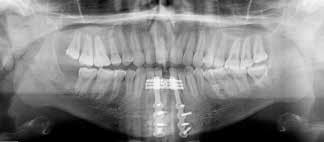

Klik ind på Tandlægebladet.dk og opret en reklamation, så sørger vi for, at bladet lander i din postkasse.

Klik ind på Tandlægebladet.dk og vælg om os

BAGGRUND – Transverselle okklusionsafvigelser kombineret med en vækstbetinget kæbedeformitet korrigeres sædvanligvis ved en sektioneret Le Fort 1-osteotomi eller kirurgisk assisteret ganeekspansion. Ved ekstreme transverselle skeletale diskrepanser mellem maksillen og mandiblen kan der være indikation for transversel udvidelse af mandiblen ved hjælp af mandibulær midtlinjeosteotomi eller mandibulær midtlinjedistraktionsosteogenese.

PATIENTTILFÆLDE – En 15-årig dreng med infantil autisme blev henvist fra Hjørring Kommunes Tandpleje til Kæbekirurgisk Afdeling, Aalborg Universitetshospital, for ortodontisk-kirurgisk behandling af et stort horisontalt maksillært overbid uden kontakt på nogen af tænderne. Den vækstbetingede kæbedeformitet blev korrigeret ved hjælp af ortodonti og mandibulær midtlinjedistraktionsosteogenese efterfulgt af en sektioneret Le Fort I-osteotomi og bilateral sagittal splitosteotomi.

KONKLUSION – Mandibulær midtlinjedistraktionsosteogenese er en forudsigelig behandlingsmodalitet til transversel udvidelse af mandiblen. Imidlertid er behandlingen forbundet med en betydelig risiko for recidiv samt biologiske og tekniske komplikationer, hvorfor mandibulær midtlinjedistraktionsosteogenese udelukkende anbefales til korrektion af ekstreme vækstbetingede transverselle okklusionsafvigelser.

EMNEORD Jaw abnormalities | malocclusion | orthodontics | orthognathic surgery

PERNILLE SAGBAKKEN, tandlæge, Odontologisk Institut, Det Sundhedsvidenskabelige Fakultet, Københavns Universitet

ANNETTE DALGAARD KJELLERUP, specialtandlæge i ortodonti, Kæbekirurgisk Afdeling, Aalborg Universitetshospital